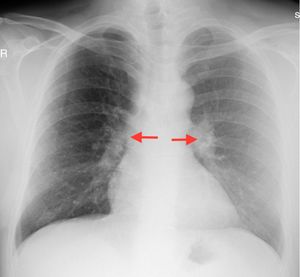

Case Report45 years old male patient diagnosed and follow-up with sarcoidosis applied to our clinic because of pain and swelling of the both ankle joints and swelling, redness and tenderness of the left first MTP joint. During examination, the patient described that previously had similar attacks in first MTP joints. Patient's physical examination showed; sensitivity of both ankle joints and swelling, redness and reduced range of motion of left first MTP joint. On laboratory tests; the acute phase reactants, serum uric acid and serum angiotensin converting enzyme (ACE) level were high (Table 1). On radiological examinations; there is no pathology on the radiograph of the ankle and toes except soft tissue swelling. Chest radiography showed enlargement in both hilar area (Fig. 1) while thorax CT showed bilateral hilar lymphadenopathy (Fig. 2). Abdominal ultrasound was normal. Serological tests was performed, negative results for rheumatoid factor (RF), antinuclear antibody (ANA), anti-cyclic citrullinated peptide antibody (anti-CCP Ab), anti-neutrophil cytoplasmic antibody (ANCA), anti-dsDNA were determined. Hepatitis markers (HBV, HCV, HIV) were normal. Monosodium urate (MSU) crystals were showed in the fluid analysis of the joint puncture. He has diagnosed with gouty arthritis and sarcoidosis according to clinical, laboratory and radiologic evaluations. Treatment with low-dose corticosteroids (prednisolone 4mg/day) and colchicine were initiated. One month later the patient complaints and laboratory findings were regressed. Six month later the radiological regression was observed on the control torax CT.